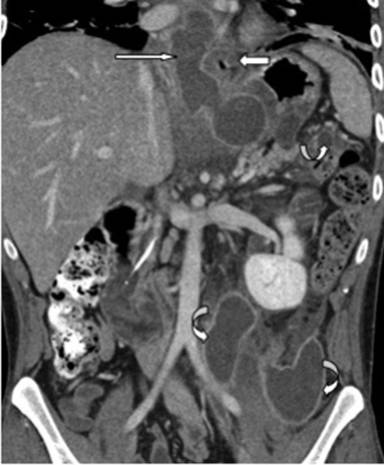

Following this he was transferred to our regional hepatopancreatobiliary surgery unit for operative management of his pseudocysts. On admission he described epigastric and left upper quadrant pain. He was tender in these areas on palpation, but the examination was otherwise unremarkable. His blood tests on admission showed a white cell count of 14.0, haemoglobin of 94, C-reactive protein (CRP) of more than 250, amylase of 141, bilirubin of 9, alkaline phosphatase (ALP) of 505 and alanine transaminase (ALT) of 30. His urea and electrolytes were unremarkable. A repeat CT scan showed multiple loculated collections extending from the left upper quadrant to just behind the left kidney and further collections extending into the left iliac fossa (Figure 1). The largest pseudocyst was shown to be passing the gastro-oesophageal junction and extending above the diaphragm. These pseudocysts seemed to be connected. It was decided to perform a cystogastrostomy and cystojejunostomy. The pancreatic pseudocyst posterior to the stomach was delineated by intraoperative ultrasound. A midline laparotomy was performed, the pancreatic pseudocyst was palpated behind stomach and again localised with intraoperative ultrasound. A longitudinal incision was made along the anterior wall of the stomach and cyst location was confirmed by aspiration of clear pancreatic fluid. The pseudocyst drained altogether 300-500 mL clear fluid which was sent for culture and biochemistry. A cystogastrostomy was performed. The position of the large, left retroperitoneal pseudocyst behind the left kidney was also located using intraoperative ultrasound and was found to be extending into the left iliac fossa. The cyst was aspirated yielding thick pus and a cystojejunostomy was fashioned onto a 70 cm Roux-en-Y loop.

Figure 1. Case #1. Coronal reformatted CT image acquired following intravenous contrast medium in portal phase. This demonstrates a well-defined, rim enhancing pseudocyst (long arrow) extending through the hiatus into the posterior mediastinum. The gastro-oesophageal junction is displaced medially (short arrow). Several further retroperitoneal pseudocysts are noted (curved arrows). |